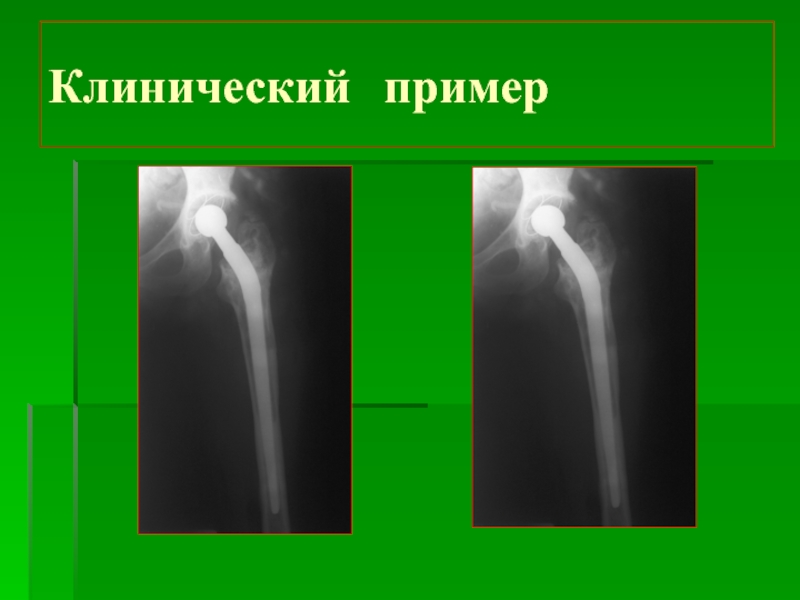

Слайд 16Клинический пример

Клинический пример